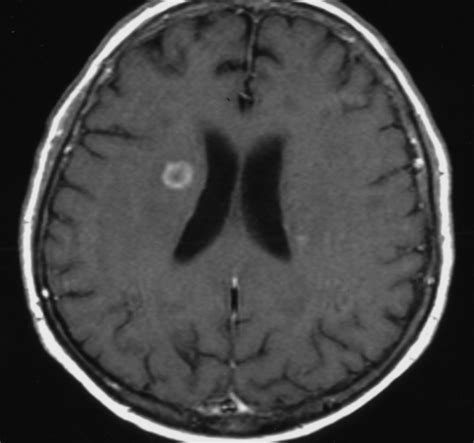

Diagnosing Pseudallescheriasis is not straightforward. It typically involves a combination of clinical suspicion, imaging studies, and laboratory tests. Doctors will often start with imaging like X-rays, CT scans, or MRIs to visualize the extent of the infection in the affected area, whether it’s the lungs, sinuses, or brain. However, these images alone can’t confirm the fungal cause. The definitive diagnosis relies on laboratory identification of the fungus . This usually involves taking a sample from the infected site – such as sputum from the lungs, a biopsy of tissue, or fluid from the cerebrospinal fluid (CSF) if the brain is suspected to be involved. These samples are then sent to a specialized microbiology lab for culture and identification. Growing the fungus in the lab and confirming it as Pseudallescheria boydii or Scedosporium apiospermum is crucial. Sometimes, molecular methods like PCR can also be used for faster identification. It’s the combination of seeing the damage on scans, observing the clinical signs, and then proving the presence of the fungus through lab work that leads to a diagnosis. Because it’s rare and can be mistaken for other conditions, early and accurate diagnosis is often a major challenge faced by healthcare providers, significantly impacting treatment outcomes. Prompt recognition and specialized testing are vital for initiating appropriate antifungal therapy and improving the patient’s prognosis. The urgency in diagnosis is paramount, especially when invasive disease affecting vital organs is suspected.

For invasive infections, particularly those affecting the central nervous system or deep tissues , surgical intervention might be necessary. This could involve removing infected tissue or draining abscesses to reduce the fungal load and make the antifungal medications more effective. Surgery carries its own risks, especially in already vulnerable patients. The prognosis for Pseudallescheriasis varies greatly depending on the site and extent of the infection, as well as the patient’s underlying health status. While localized infections, like a skin or sinus infection, might be treatable with a combination of surgery and antifungal therapy, invasive or disseminated disease, especially in immunocompromised individuals, carries a high mortality rate. Brain infections, in particular, are often devastating. Even with aggressive treatment, recovery can be slow and incomplete, and the risk of relapse is always a concern. This is why Pseudallescheriasis remains a serious concern in clinical medicine, necessitating ongoing research into more effective diagnostic tools and therapeutic strategies. The complexity of treatment and the often guarded prognosis underscore the critical need for early detection and prompt initiation of specialized care for individuals suspected of having this challenging fungal infection. The interplay between the fungus’s inherent resistance, the patient’s immune status, and the availability of effective treatment options makes each case a unique and often uphill battle.